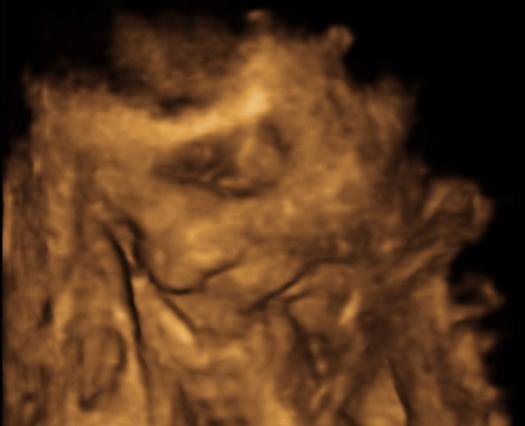

Men hvor var det vidunderligt at se sin lille generte, puttemand, der ikke syntes det var spor sjovt at to kvinder ville se ham mellem benene, så benene blev da krydset og hånden hjalp lidt til. Ansigtet puttede vi lidt væk i starten, men da mor så nussede hvor det lå, vendte man da lige ansigtet en smule og smilede stort